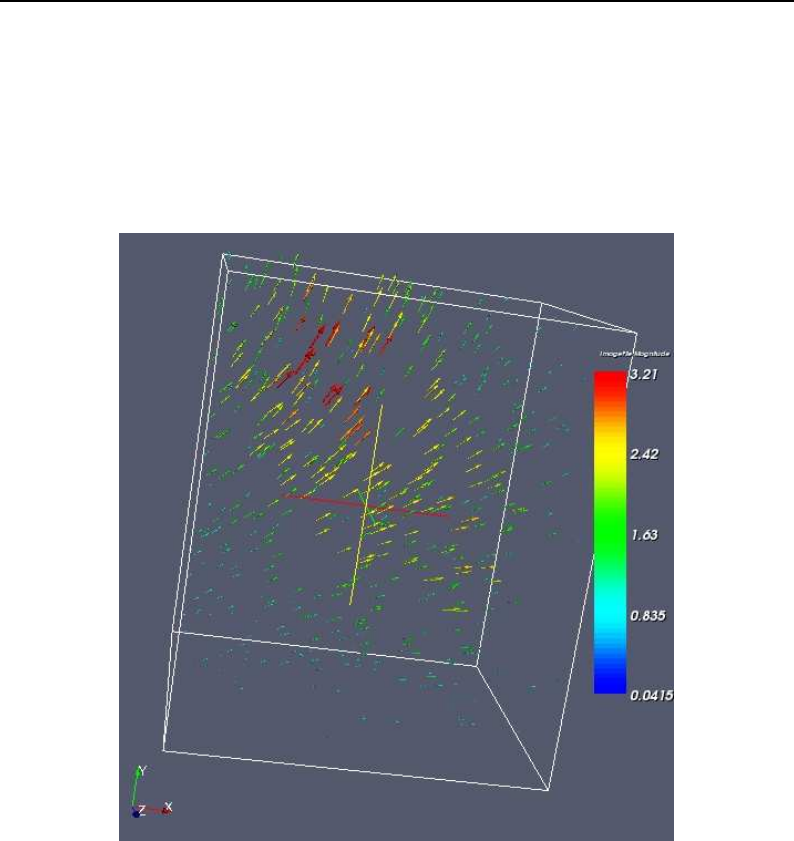

- Deformable Registration

- Demons Deformable Registration

- Visualizing Deformation fields